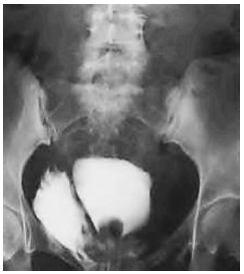

Paciente masculino, 26 anos, admitido em pronto socorro com queixa de dor pélvica após se chocar com objeto fixo ao conduzir motocicleta. Após avaliação inicial, foi realizada a cistografia registrada na imagem a seguir. A uretrografia não mostrou sinais de lesão uretral, e não havia evidência de fratura pélvica.

Após análise do caso clínico e da imagem, qual dos tratamentos a seguir é o mais apropriado para condução inicial do paciente?